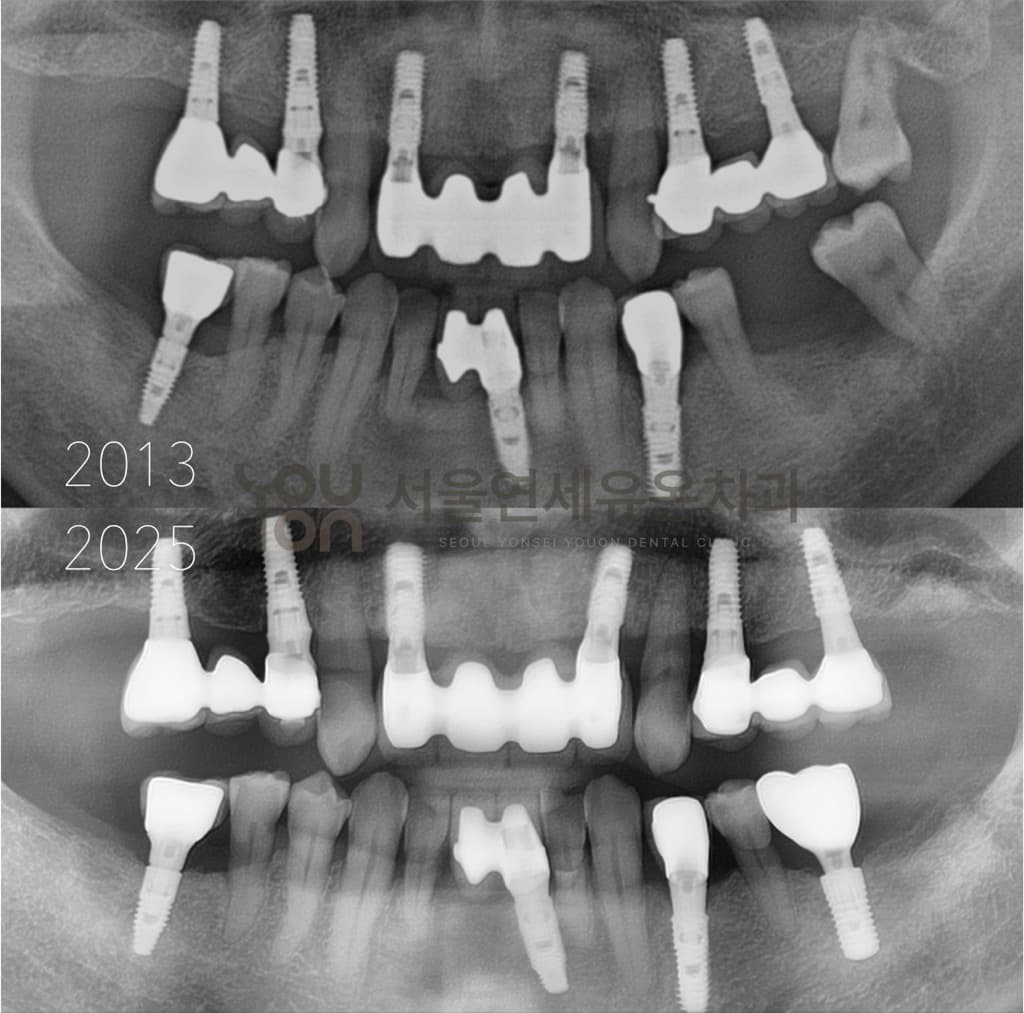

치료 전후 비교

치료 전

치료 후

본 이미지는 촬영 조건에 따라 실물과 일부 다르게 보일 수 있으며, 환자 본인의 동의를 얻어 촬영 후 게재하였습니다.

치료 결과는 환자 개개인의 상태에 따라 다르며, 치과의사의 상담이 필요합니다.